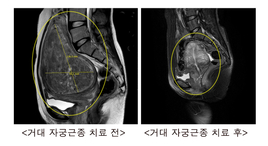

“거대 자궁근종도 수술 없이 치료한다”